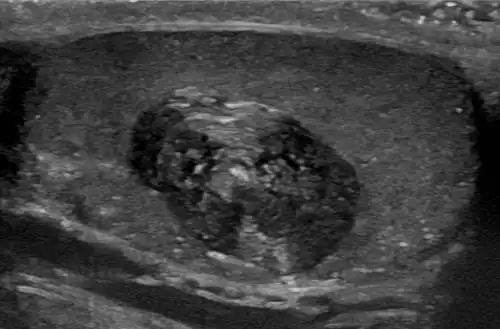

Kyste épidermique d'un testicule à l'échographie, d'aspect lamellé (« peau d'oignon »)